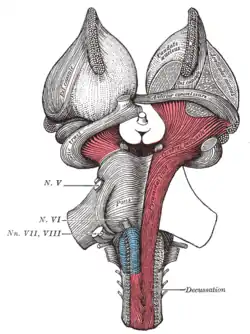

Deep dissection of brain-stem. Lateral view. Superficial dissection of brain-stem. Ventral view.

Superficial dissection of brain-stem. Ventral view. Dissection of brain-stem. Dorsal view.